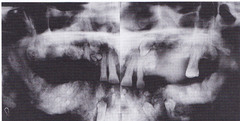

MOST COMMON EXTRA TOOTH -extra tooth seen at the midline of the anterior maxilla

-Asymptomatic-very large may cause expansion of lingual aspect of mandible -well circumscribed radiolucency below the apicies of the mandibular incisors